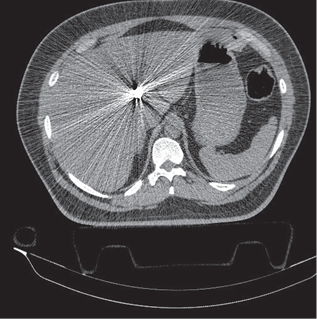

On computed tomography (CT) scan view was possible to see the bullet on the right lobe of the liver. A CT of the chest and abdomen revealed hemopericardium, a small pneumopericardium (Figure 2), and the bullet on Couinaud’s segment IV of the liver (Figure 3).

At laparotomy, moderate amount of free blood was found in the peritoneal cavity, a blunt injury with active bleeding in Couinald’s segment IV of liver, and 5 cm injury in the central tendon of the diaphragm. The liver was treated with vertical U stitches of chrome catgut 0, the diaphragm was repaired with horizontal U stitches of polypropilene 0.